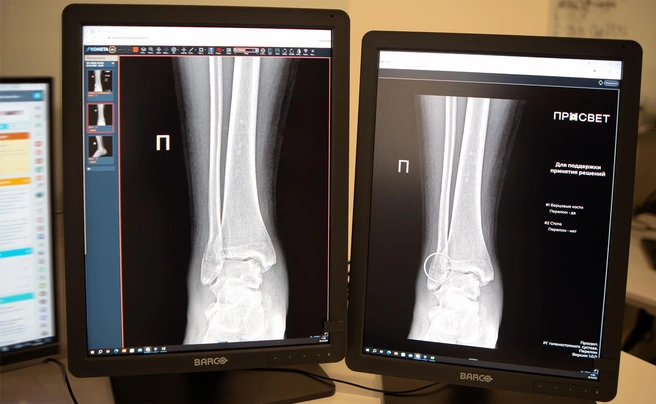

— Цифровые решения уже более пяти лет помогают столичным рентгенологам прежде всего в анализе медицинских снимков. Недавно мы запустили два новых ИИ-сервиса, которые помогают обнаруживать на рентгеновских изображениях травмы костей голеностопного и лучезапястного суставов — одних из самых функциональных и при этом уязвимых. Алгоритмы автоматически отметят поврежденные участки и выполнят необходимые измерения, даже если на снимке присутствуют признаки сразу нескольких переломов. Сегодня в распоряжении московских рентгенологов уже более 60 ИИ сервисов. Одни отличают «норму» от проявления заболевания, другие, например, могут измерять границы и размеры патологии, — рассказала Анастасия Ракова.

ИИ-технологии для лучевой диагностики анализируют снимки по множеству параметров, помогают выполнить необходимые расчеты и положительно влияют на увеличение скорости описания снимков. Помимо этого, они могут заметить даже самые минимальные трещины и акцентировать внимание врача на том, что в этой области не один, а несколько переломов. Правильно выявленные обстоятельства влияют на тактику успешного лечения.